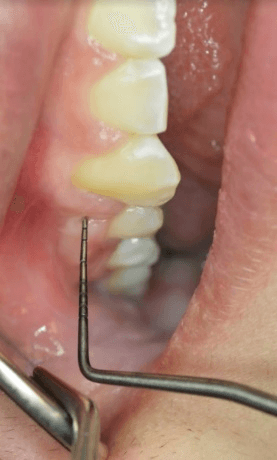

Measurements were made in the x, y, and z planes to determine gingival cleft severity. Figure 4 demonstrates a gingival cleft between the upper right second premolar and canine with the periodontal probe just outside of the cleft. Figure 5 Illustrates the same site with the periodontal probe inside the cleft in the Z direction (occlusal-gingival). Figure 6 Illustrates probing depth of the gingival cleft in the Y direction (bucco-lingual).

Figure 6: Gingival cleft with periodontal probe in Y direction.